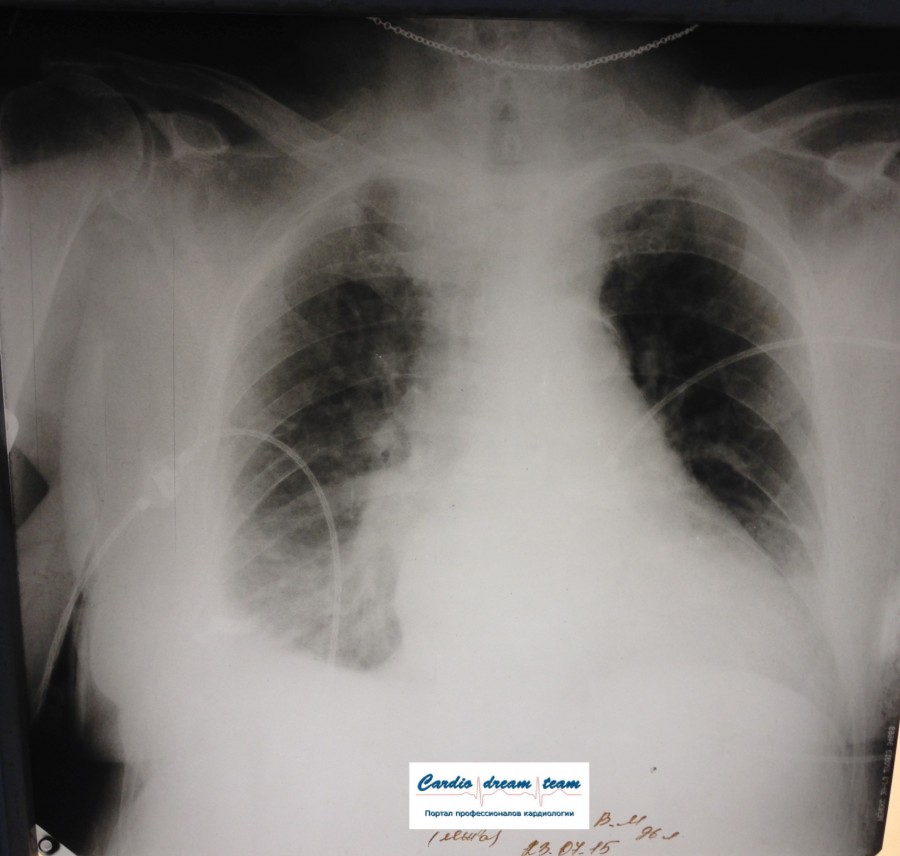

Не обсуждалась Дата 23-ИЮЛ-15 ОПИСАНИЕ: Проведена рентгенография органов грудной клетки в прямой проекции, положение лежа, условия ПИТ Легочные поля: неравномерно прозрачны за счет сосудистого обогащения, в базальных отделах с обеих сторон, отмечается сгущение легочного рисунка, за счет гиповентиляции, в плевральных полостях жидкость Легочный рисунок: Изменен по смешанному типу: обогащен за счет сосудистого компонента, деформирован за счет склероза. Корни: бесструктурны, расширены за счет сосудистого компонента, обогащены Синусы: определяется наличие жидкости по линии 5 ребра Сердце: широко лежит на диафрагме отмечается расширение границ сердечной тени влево, вправо экг-электроды. ЗАКЛЮЧЕНИЕ: Рентген-признаки 2-х стороннего гидроторакса с гиповентиляцией базальных сегментов.. Признаки застоя по МКК 2 степени (умеренно выраженный). Пневмосклероз. Р-признаки гипертрофии левого желудочка сердца. Склероз аорты.